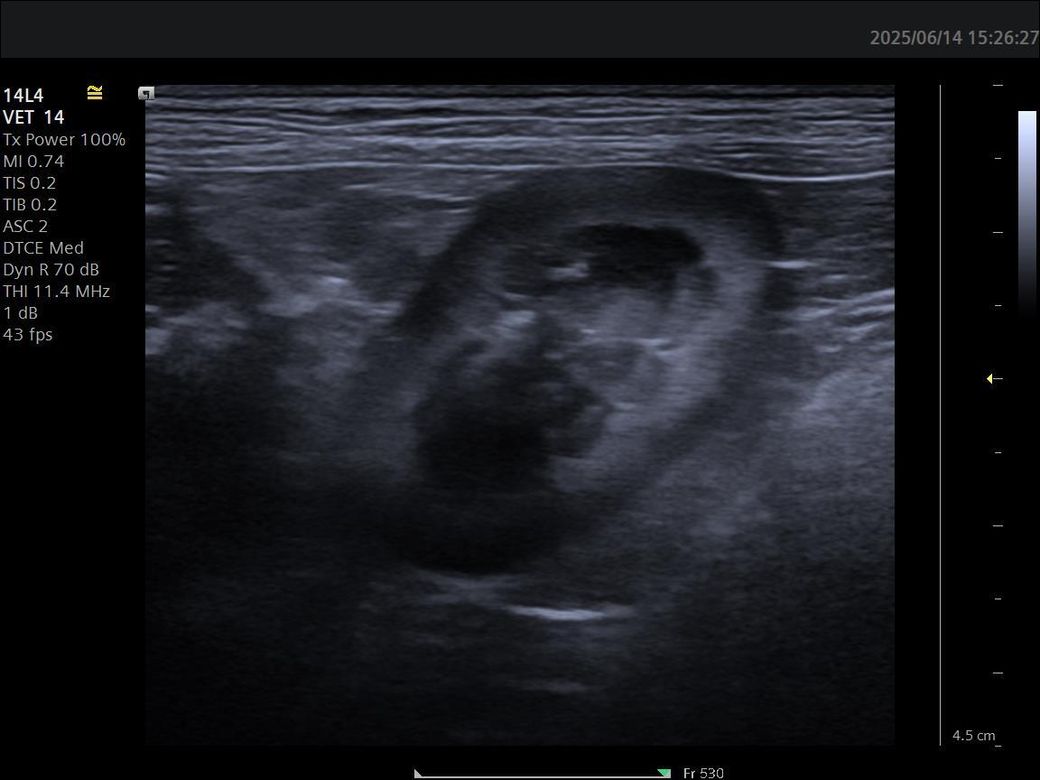

강아지 신장 사진입니다.이상한부분있을까요

4살 8개월 비숑인데 신장혈액상으로 정상인데 사진으로 어떤분이 궁상동맥 석회양상이보인다고하는데 궁상동맥 석회양상이라는게 석회화로진행되지는 않고 그전단계라는건가요?그거 없앨려면어떻게해야하나요

없어지지 않습니다. 일반적으로 정상적인 노령성 변화로 궁상동맥 벽에 칼슘과 같은 무기질이 침착된 양상을 의미합니다. 큰 의미를 두지 않는 변화입니다.